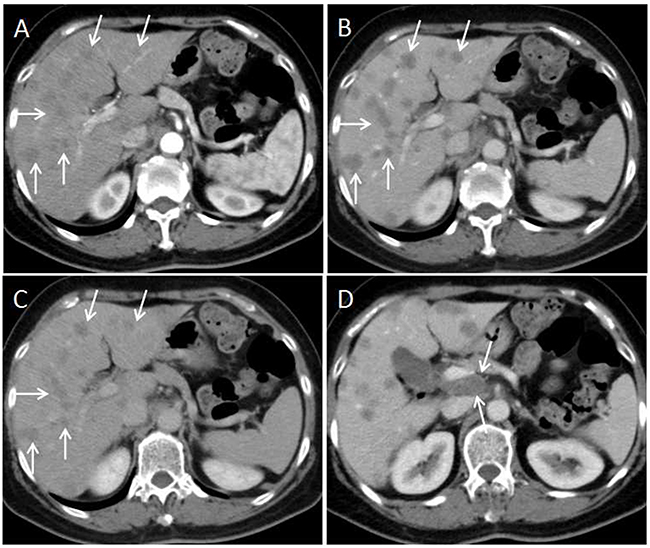

Figure 5: 63-year-old woman with moderately differentiated colon adenocarcinoma. (A) Multiple hypo enhanced liver metastases are presented on hepatic arterial phase CT image(arrows). (B and C) On the portal venous phase and equilibrium phase images, the lesions keep hypo enhancement that meets the plateau enhancement pattern(arrows). (D) Axial CT image on the portal venous phase presents lymphadenopathy between the portal vein and venae cava inferior (arrows).